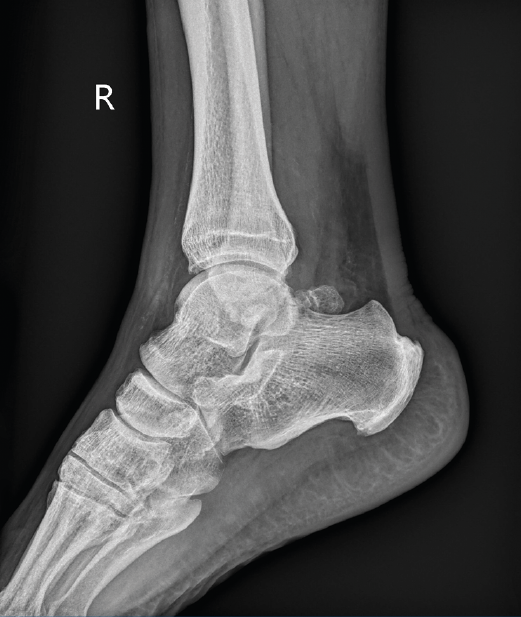

Figura 1. Os trigonum en radiografía simple.

Como etiología de dicho dolor se encuentra la afectación ósea (83% de los casos), con el os trigonum (Figura 1) presente en hasta el 8% de la población, la fractura de Shepherd o un tubérculo de Stieda prominente(4). Dentro de la patología de las partes blandas, el flexor largo del hallux (FLH) (Figura 2), en forma de tendinopatía, tenosinovitis estenosante, nódulos, etc., puede originar dolor en el compartimento posterior(5).